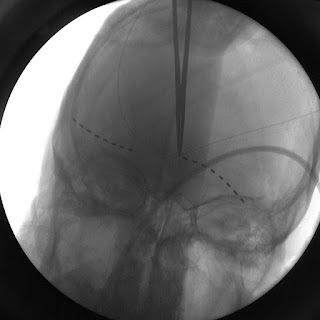

It started with little things. For a long time and even now bending over made me light-headed, Laying on my back without a pillow was the worst. It came along with nausea. Being unsteady. It took me a full year to be able to tie my own shoes without falling forward. It took 6 months before I started to get feeling back on the right side of my head. Weirdest feeling washing your hair, and have no clue if soap or even water is touching your head. Coming from a guy with such a sensitive scalp from headaches. I literally feel every strand on my head. The feeling came back in my head 100%. The goose egg where they drilled into my head is fine. I can tap it with my hand and feel no pain. The wires coming out of my brain to where they connect to go to my pacemaker is extremely sensitive. Even the pillow on my bed bothers me. The pacemaker floats in my chest and is discomforting but tolerable with adjustment.